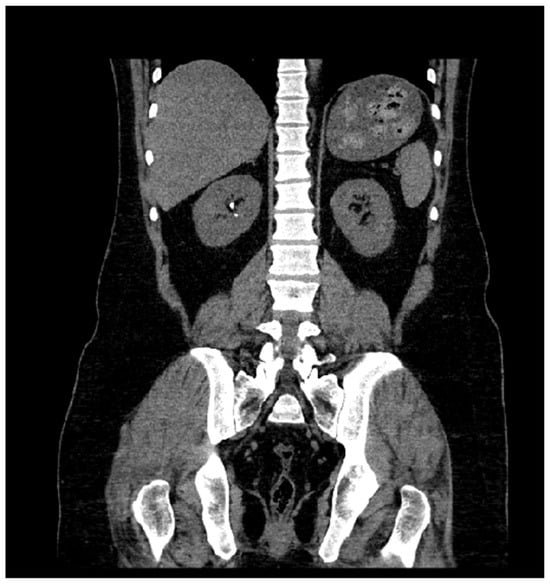

Optimizing Scan Range in Computed Tomography of Kidneys, Ureters, and Bladder: A Retrospective Study on Reducing Overscanning

3. Results